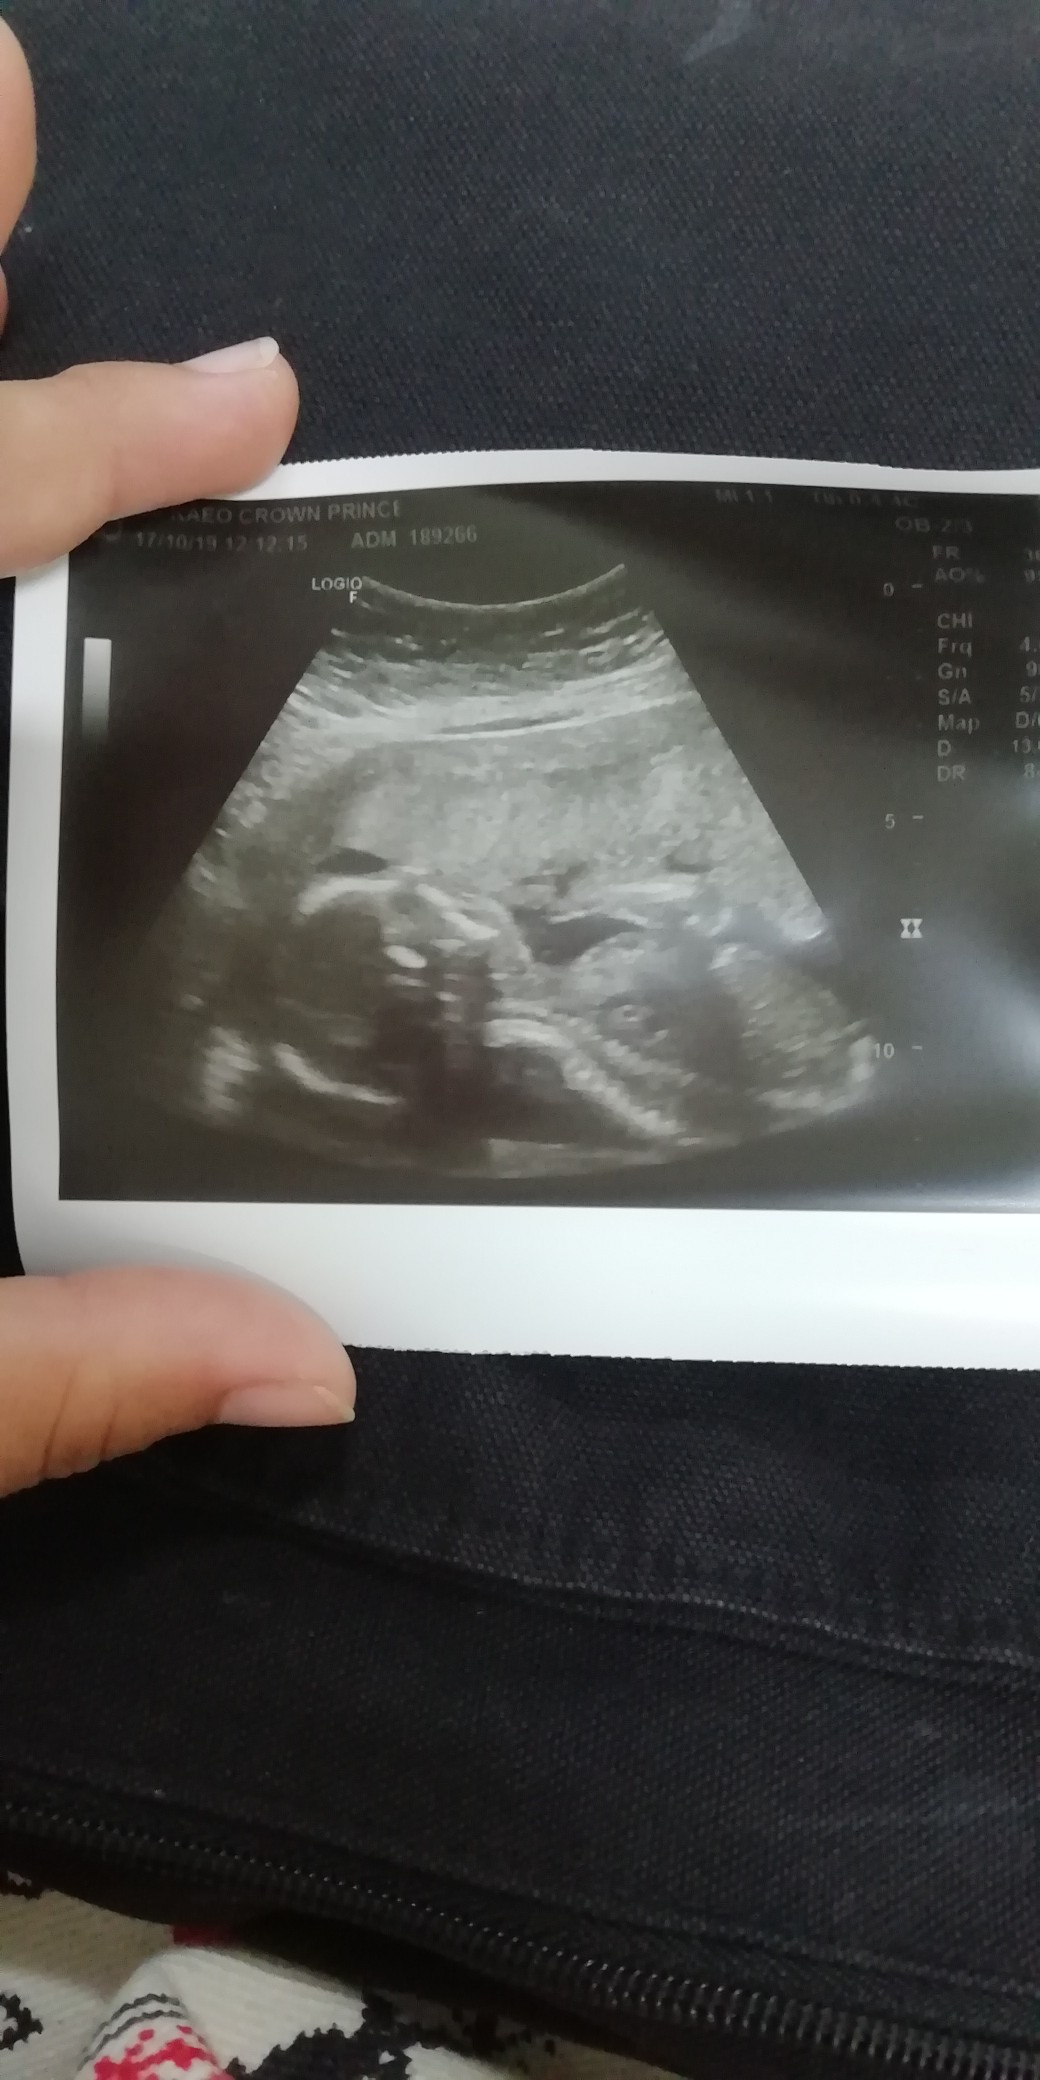

บ้านนี้ น้องนอนคว่ำค่ะ 555

19 week 6วัน ตามเครื่องซาวเลย